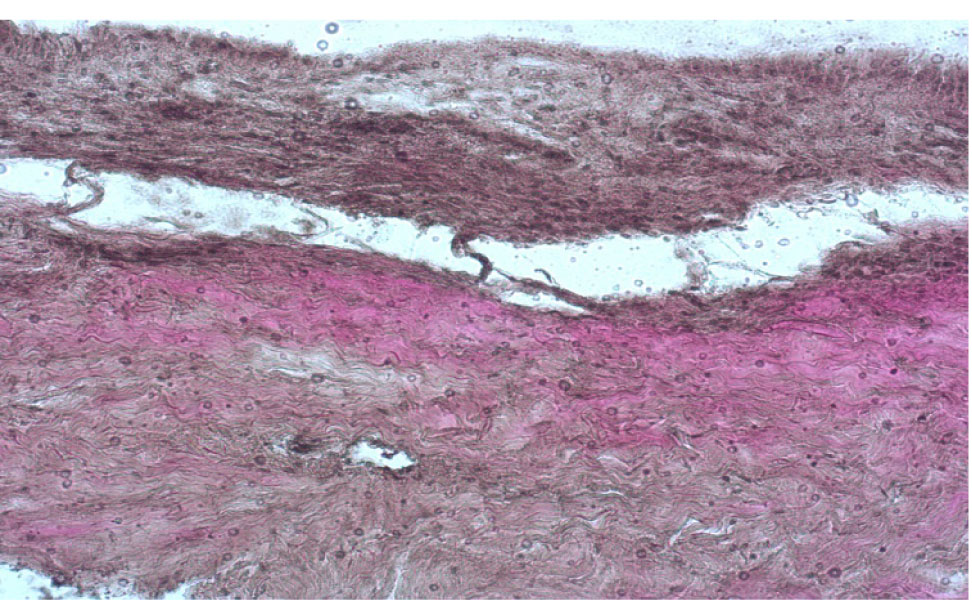

В первой группе в эксперименте полностью удалялся передний эпителий роговицы в зоне диаметром 8,0 мм. В препаратах роговицы, окрашенных по Ван Гизону, при полном отсутствии эпителия наблюдалось сохранение боуменовой мембраны в виде поверхностной гомогенной пластинки, в поверхностной строме – разобщение пучков коллагеновых волокон, появление обширных сливных межламеллярных лакунарных пространств между передней и средней стромой. При этом в толще средней и задней стромы наблюдались явления отека, инфильтрации ткани (рис. 5).

Рис. 5. Роговица свиного кадаверного глаза после полной механической деэпителизации, окраска по Ван Гизону, об. ×10